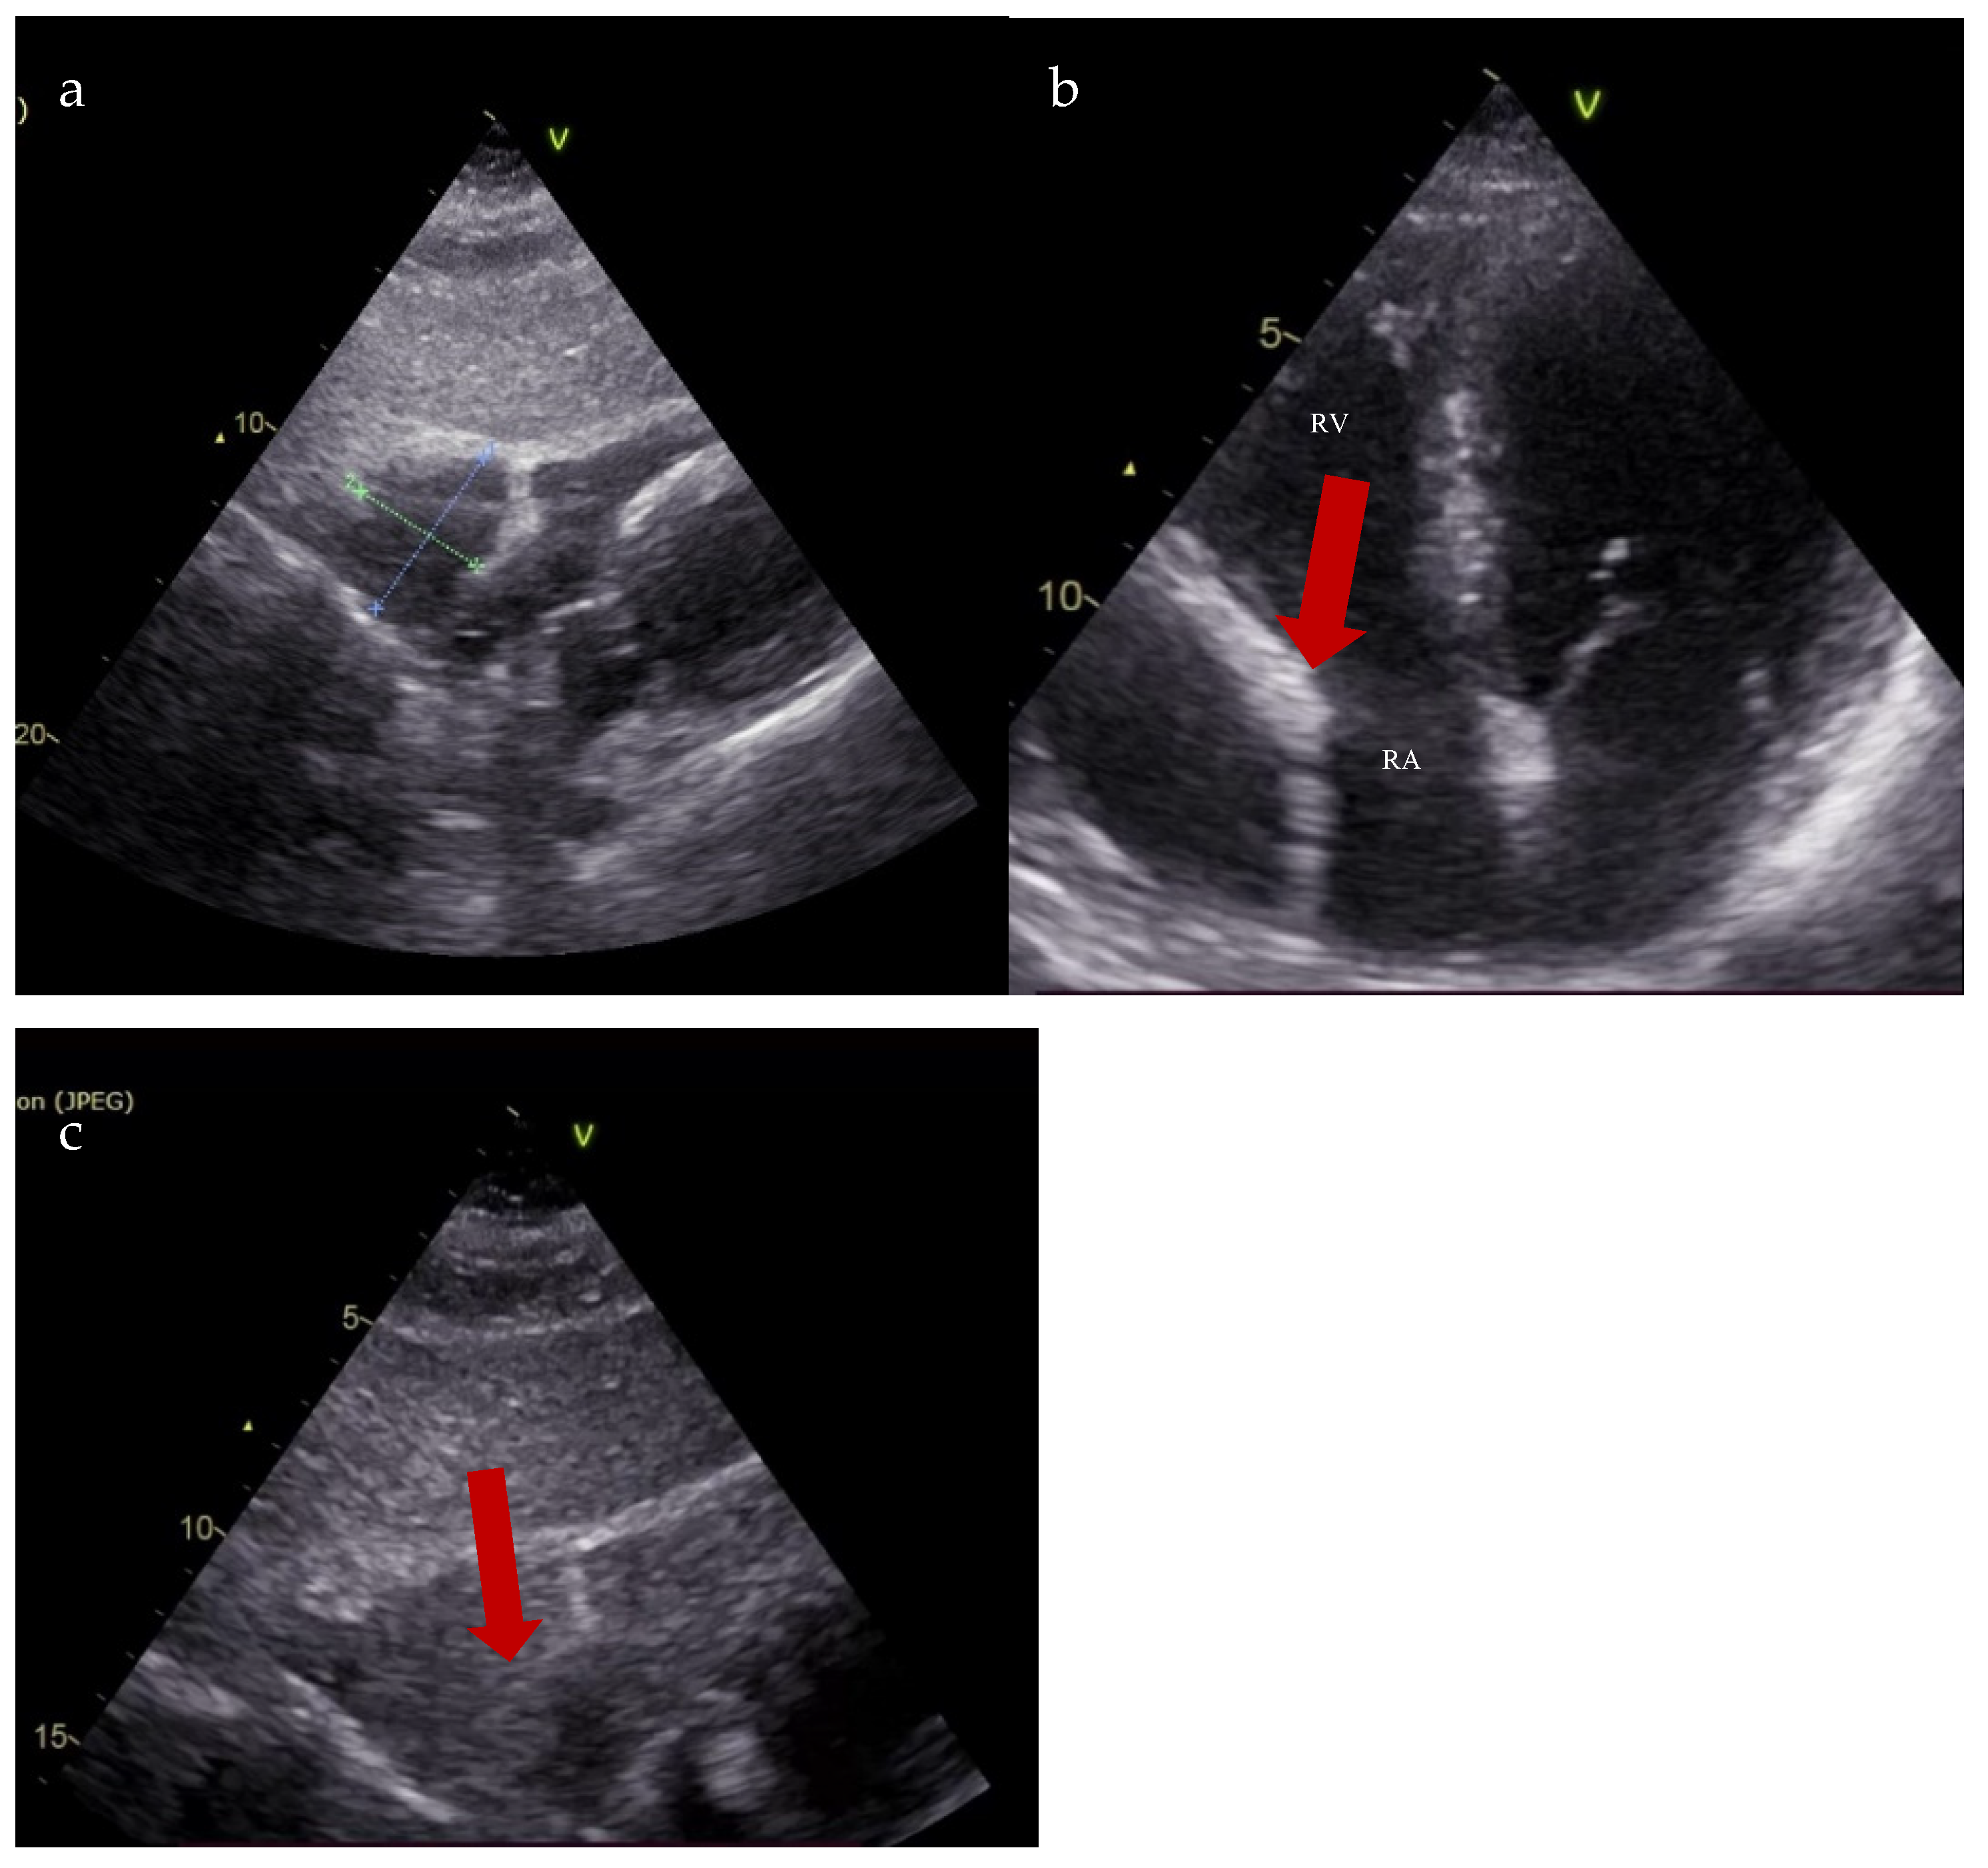

Due to the increased size of the diverticulum and the associated high risk of rupture, the patient was referred to the Cardiovascular Surgery Department, where a successful resection of the lesion was performed (Figure 5). The histopathologic examination confirmed a bistratified wall consisting of a thin endothelium and fibrous tissue with peripheral collagenization, suggestive of a diverticulum. The patient followed the same treatment as before with doses adjusted to clinical and paraclinical data (carvedilol 3.125 mg twice a day, sacubitril/valsartan 24/26 mg twice a day, dapagliflozin 10 mg once a day, spironolactone 50 mg once a day, and rosuvastatin/ezetimibe 40/10 mg once a day).

Figure 5.

Intraoperative visualization of the right atrium diverticulum (black arrow).